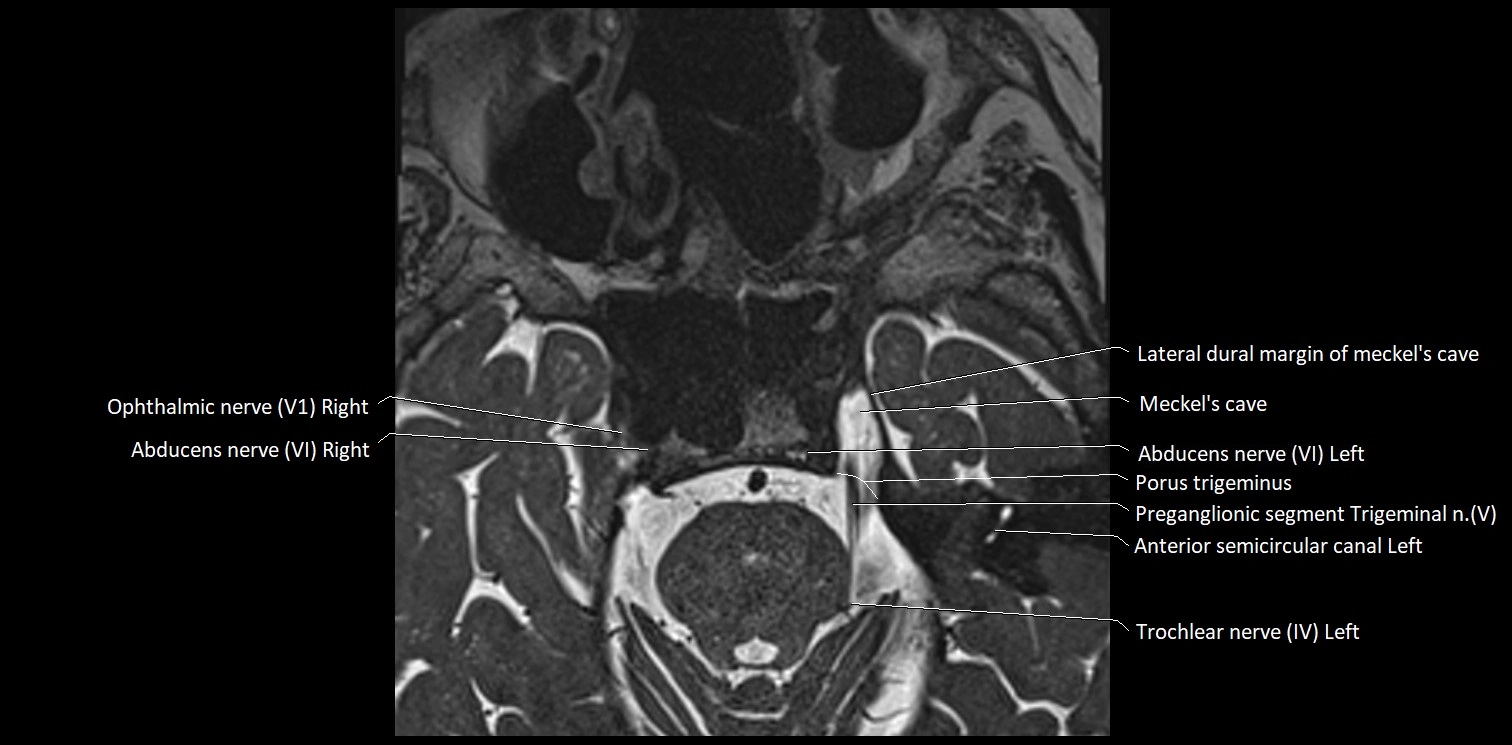

MRI Appearance

• The abducens nerve is a small, thin, linear structure

• Best visualized on high-resolution T2-weighted 3D MRI sequences (e.g., FIESTA or CISS)

• Seen as a hypointense (dark) line running from the brainstem at the pontomedullary junction, traversing the prepontine cistern, and entering Dorello’s canal under the petrosphenoidal ligament, then into the cavernous sinus, and finally the orbit

• May be challenging to visualize in standard MRI due to its small size

• Pathology may be inferred by absence, displacement, or enhancement of the nerve

MRI images

image